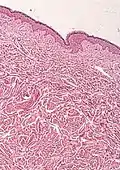

Microscope with stained slide (histological specimen)

Histopathology of BOS[12]